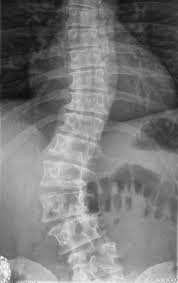

特发性是脊柱畸形的较常见原因,主要是引起脊柱侧凸。从病因学上来讲,并不十分明确,但是和基因和遗传具有一定关系,此外还存在椎旁肌肉本身分布不平衡的原因。形态学是指椎体本身没有结构异常,椎体分隔正常,拥有对称的椎弓根,发育正常的椎板和关节突。 》》》百看不如一问,咨询专家如何对症治疗

特发性脊柱畸形即原因不明的脊柱畸形,这部分患者约占80%。其发病原因目前为止可认为与下列因素有关: